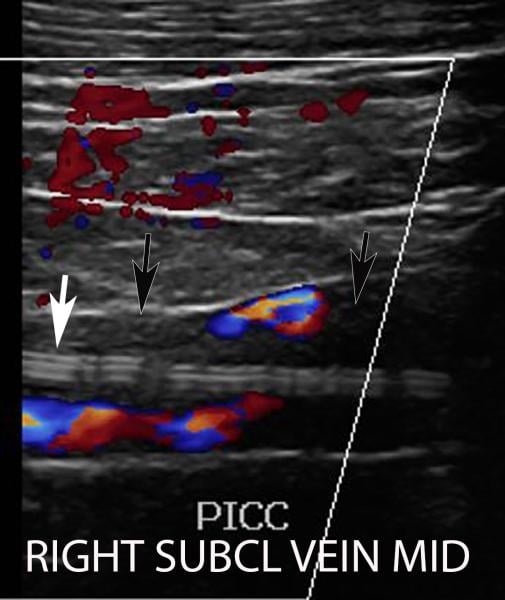

This photo gallery shows the variety of radiological presentations of COVID-19 (SARS-CoV-2) in medical imaging, including computed tomography (CT), radiograph X-rays, ultrasound, echocardiograms and magnetic resonance imaging (MRI). The radiology images show examples of typical COVID pneumonia in the lungs and the numerous complications the virus causes in the body in multiple organs, including the brain, kidneys, heart, abdomen and vascular system.

Ultrasound, especially hand-held ultrasound imaging devices, have become a primary imaging modality for novel coronavirus because of the ease to bag the device and sterilize it after use. CT and mobile X-ray systems are also used as front-line imaging systems for COVID-positive or suspected COVID patients.